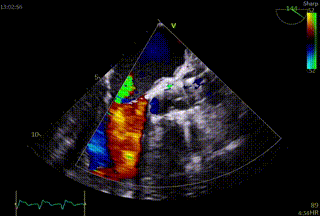

术前与术后超声,瓣口面积从0.6cm²提升至 2.2cm²,血流动力学优异。